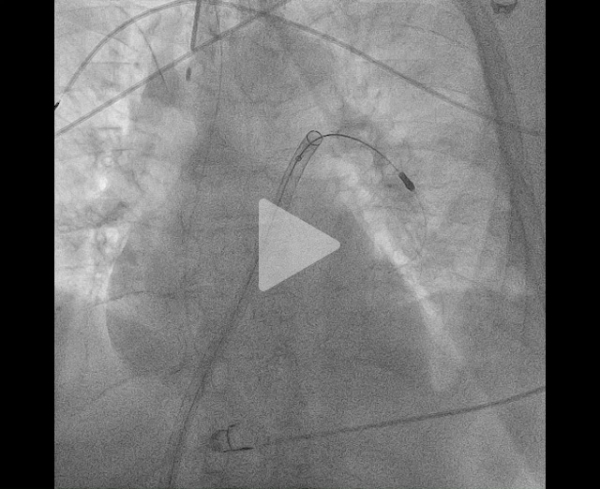

Il s’agit d’une procédure réalisable sous anesthésie locale, par voie fémorale écho-guidée (introducteur de grand diamètre – 24F) et sous monitoring de l’efficacité de l’héparinothérapie. Une cathétérisation sélective des 2 branches de l’artère pulmonaire est réalisée permettant la confirmation d’une hypertension pulmonaire initiale (mesurée à ici à 67mmHg pour la PAPs) (Figure 8), la mise en place d’un cathéter dédié de thromboaspiration permettant de ramener le thrombus (Vidéos 2, 3 et 4). À visée d’épargne sanguine, chaque aspiration est filtrée pour permettre une réinjection du sang.

Figure 8 : évaluation initiale des PAPS

Vidéo 2 : angiographie initiale